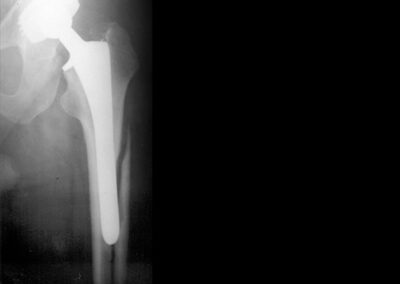

- Luxação: pode ocorrer em até 3% nas artroplastias primárias e em até 10% nas revisões. A luxação ocorre mais comumente até seis semanas da cirurgia, mas pode ocorrer muitos anos após o procedimento cirúrgico, acompanhadas por soltura dos componentes. Pacientes que apresentam luxações traumáticas agudas tem melhor resposta à redução e imobilização Fig. 16.

Fig. 16. Exemplos de luxação de prótese total de quadril pelos mais diversos motivos.